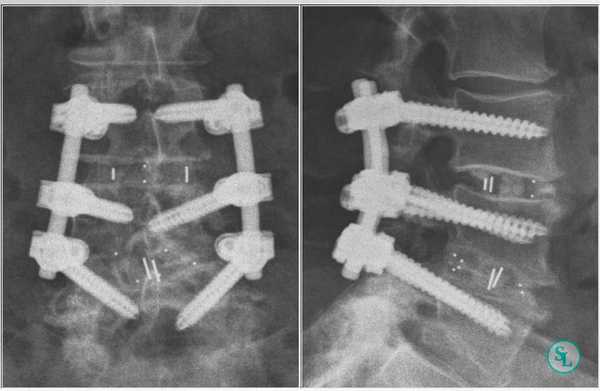

Стабилизационная система на рентгене.

В большинстве случаев проблемный сегмент стабилизируют с помощью металлоконструкций, чаще представленных транспедикулярными системами и пластинами с винтами из высокотехнологичных сплавов металла. В хирургии такая техника называется инструментацией позвоночника. Кроме металлоконструкций, для стабилизации также могут быть применены полимерные устройства, сделанные, например, из углеводородного волокна или резорбирующегося высокомолекулярного биополимера. К отдельной разновидности стабилизирующих вмешательств, которые не причисляют к инструментации, относят установку кейджей имплантатов межпозвоночных дисков.

Системы стабилизации позвоночника жесткого типа

Жесткие, или неподвижные металлоконструкции подразумевают закрепление позвонков в постоянном фиксированном положении. Устанавливаются они из заднего доступа (со стороны спины) под контролем КТ и рентген-аппаратуры. Крепятся к позвонкам резьбовыми винтами, которые погружают в костные тела на глубину до 80%. Рекомендуют ставить подобного плана системы сугубо в безальтернативных случаях, если ни один другой вид лечения не сможет решить проблему с поврежденным отделом позвоночника.

Охарактеризуем самое распространенное средство неподвижной фиксации позвоночника - транспедикулярное устройство на примере системы «Криптон» (Krypton®). Это - востребованная модель ТПФ в спинальной нейрохирургии. Ее производит ведущая немецкая компания Ulrich Medical GmbH.

Спинальные хирурги не только Германии, но и всего мира высоко оценили изобретение передового производителя. В первую очередь за уникальные конструктивные особенности. По словам специалистов, систему «Криптон» отличает эргономичность, простота, безопасность в установке, что в значительной мере облегчает труд хирурга. Она высокоэффективна в декомпрессии нервных структур, устранении деформаций и нестабильности позвоночника. Подробнее об расскажем далее.

- Система создана для универсальной фиксации торакального и люмбального отделов позвоночника. Представляет собой «умную» комбинацию из титановых стержней и винтов, способствующих быстрому и качественному формированию артродеза.

Стабилизация поясничного отдела.